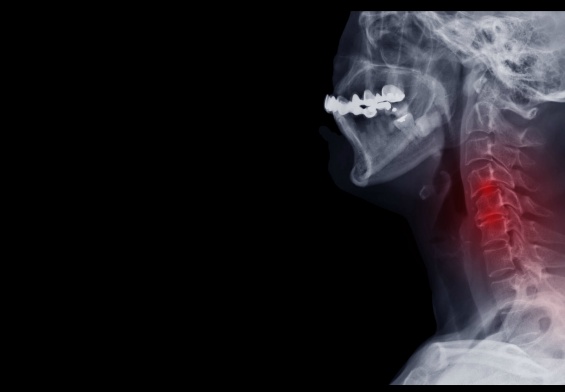

The trigeminal nerve and facial pain

The trigeminal nerve carries sensation from your face to your brain. When it’s compressed or irritated, it can misfire in dramatic ways.

- MRI to look for:

- A blood vessel compressing the trigeminal nerve

- Multiple sclerosis plaques

- Tumors or other structural problems